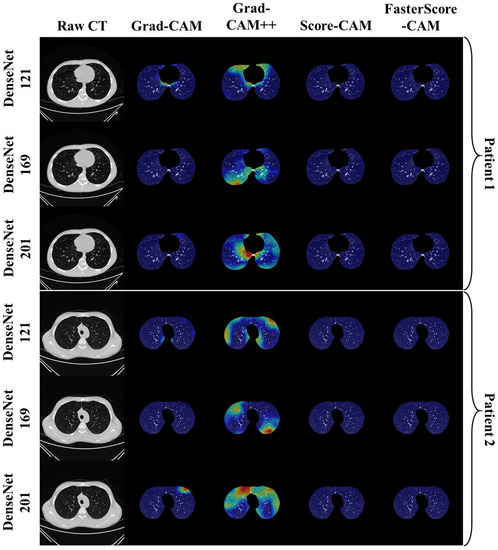

Visual Results Representing Lesion Using the Four CAM Techniques